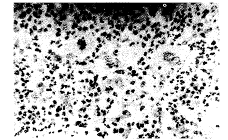

瘤组织变化: ① 光镜观察:瘤外组:20例行切除或切检,3例较多变性、坏死,其余不明显。瘤内组: 25例行切除或切检,多数有明显坏死及淋巴细胞浸润等(图1,2)。7例标本瘤周组织连续切片观察未发现注射针道(以美蓝标记)有瘤细胞。② 电镜观察:淋巴细胞包围瘤细胞并与之融合,瘤细胞线粒体肿胀。

图1 阴茎亚性纤维组织细胞瘤(治疗前),镜下见病理性核分裂(HE×200)

图2 治疗后瘤组织坏死(HE×200)